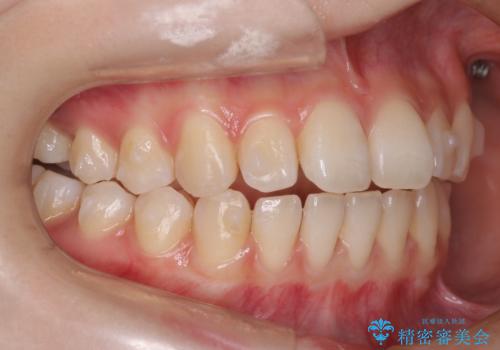

【前歯で噛めません、すきっ歯も気になります】インビザライン治療症例

- 前歯の見た目と噛み合わせの改善を希望され来院された患者様です。

初診時の歯並びの状態としては、上下前歯が噛んでいない開口という状態であり、前歯を中心に上下とも歯の間に隙間がある状態でした。

抜歯は行わずマウスピース治療による主訴の改善を計画しました。

また、開口、スキッ歯の根本的な原因として考えられる、舌突出癖による後戻りの防止のためにMFTという舌のトレーニングも行いました。

見た目、嚙み合わせ及び、治療期間や施術内容に大変ご満足いただきました。